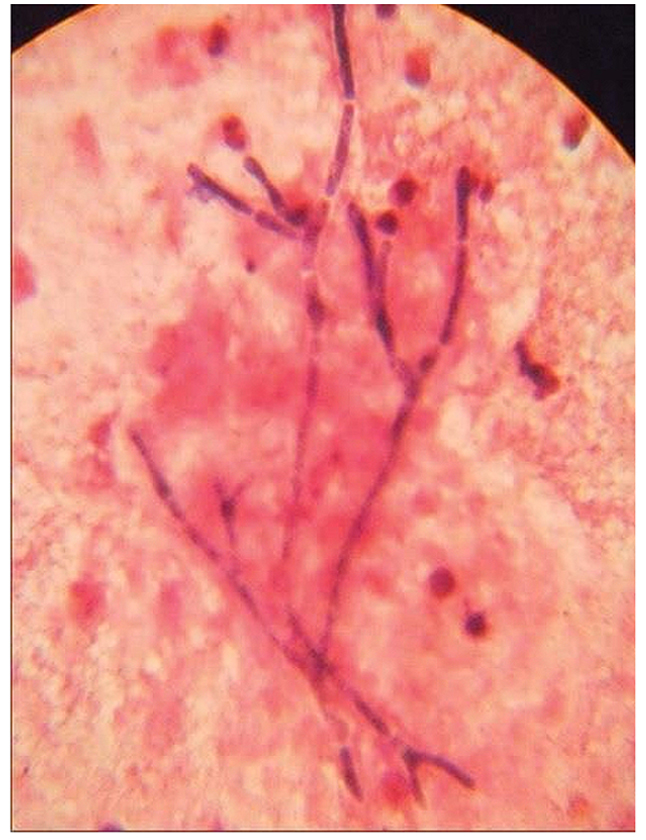

The condition usually responds well to antifungals. Here we are reporting a case of primary aspergillosis of the vocal cord in a patient without any underlying risk factor. Histopathology examination showing septate dichotomously branching hyphae (Figure 2).

Figure 2. Histopathology

Specimens collected from the patient for the diagnosis of aspergillosis include tissue, aspirates, and fluids like broncho-alveolar lavage. The tissue must be sent in a sterile tube or container and formalin fixed. Stains used for examination of fungal species include periodic acid Schiff (PAS), Gomori’s Methenamine Silver stain (GMS) and calcofluor white. Septate, dichotomous branching hyphae are observed. The histopathology of invasive fungal Aspergillosis shows pale necrotic mucosa as fungal angioinvasion causes infarction.